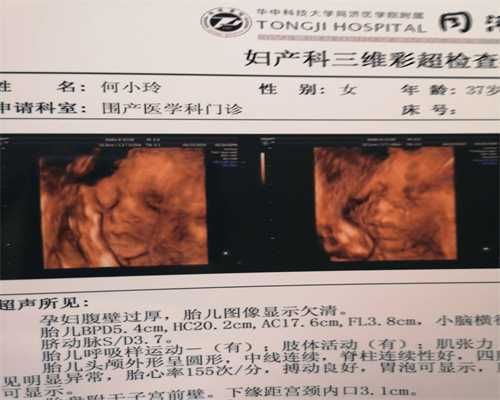

五、查验B超时,也有好几个卵子囊性灶,双合诊及其B超见子宫卵巢肿胀;腹腔镜手术见子宫卵巢子宫内膜肥厚型。